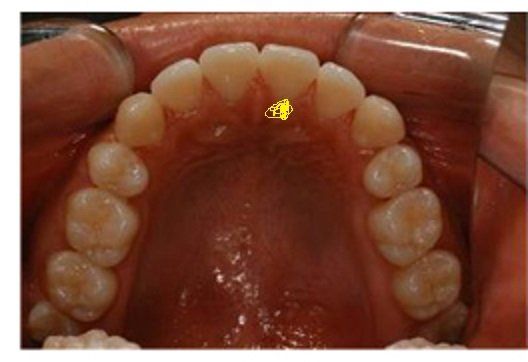

잇몸이 퇴출 되고요. 거기에 치석이 자주 끼는 것 같고 제가 노랑 표시 한 곳이요. 저 부분 관리가 힘들어요.

• 1번 째 사진

구강내에서 치석이 가장 잘생기는 부위입니다. 하악 전치 쪽에는 침샘이 있어서 치석이 잘생깁니다. 양치하실때 칫솔을 세워서 닦으시고 정기적으로 치과가셔서 치석이 있으면 제거하는게 가장좋은 방법입니다

31,41이라면 아래치아의 중앙치아를 의미합니다.

이 부위는 치석이 잘 끼는 부위입니다. 칫솔모를 수직으로 세워서 하면 칫솔질이 가능합니다.